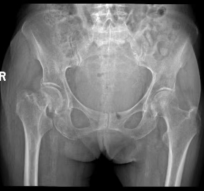

81 岁的闫爷爷和 89 岁的暴奶奶均因意外跌倒导致髋部骨折,来院寻求治疗。对于 80 岁以上的老人,髋部骨折是一项严峻的健康挑战。若采取保守治疗,长期卧床极易引发肺部以及泌尿系感染、深静脉血栓、压力性损伤等一系列致命并发症;而手术治疗则需综合评估患者身体机能、麻醉耐受度及合并多种严重疾病及术后恢复慢等重重难关,手术风险极高。

术后复查的 X 线片显示,两位老人髋关节置换位置均非常理想,为后续康复锻炼提供了必要条件。在医护团队的精心指导和鼓励下,两位老人术后第三天便成功下地站立、行走。